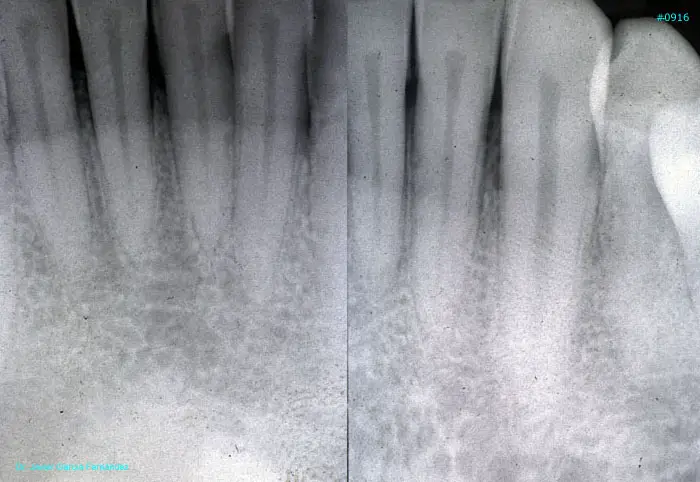

Atlas of Surgical Techniques in Periodontics. Chapter III. Atlas de Técnicas Quirúrgicas en Periodoncia